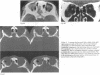

Periorbital dermoid cysts should be removed because they commonly leak their irritant contents into the surrounding tissues. The underlying bone may, however, be involved in patients with dermoid cysts at the outer canthus. Computed tomography studies of 70 patients (43 men and 27 women, aged 30 months to 63 years, mean 29 years) with proved dermoid cysts of this type were reviewed. The lesion was always unilateral; 34 were on the left. The bone of the lateral wall and superotemporal angle of the orbit showed the following abnormalities, often in combination: pressure erosion in 61 cases and an otherwise abnormal shape, probably developmental, in 55; the dermoid cyst entered a tunnel or canal through the lateral wall in 24; a blind pit or crater in 15; and a cleft in 20; many patients also showed abnormal bone texture. These findings are extremely important for planning adequate surgery, and indicate that bony involvement is much more frequent than previously appreciated.